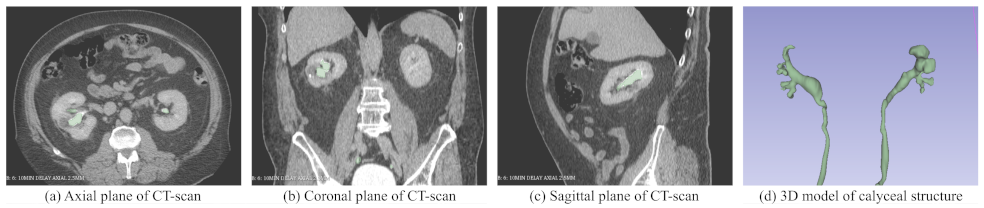

3. Generating 3D Model Patient CT Scans

3.1. Method